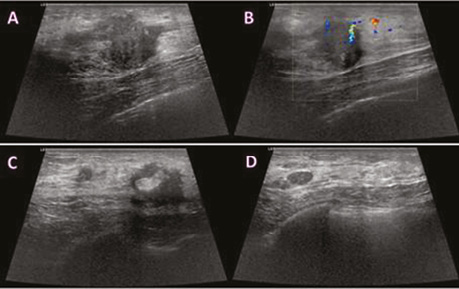

Виконано УЗД МЗ на діагностичному ультразвуковому приладі LOGIQ S7 Expert, GE Ultrasound Korea Ltd, Республіка Корея. У правій МЗ на 1 год визначалося гіпоехогенне гетерогенне новоутворення неправильної форми з нечіткими нерівними контурами, розміром 29×23×18 мм, з ознаками локусів інтранодулярного кровотоку при кольоровому доплерівському картуванні (КДК). Поруч візуалізувалися аналогічної структури: 3 новоутворення розміром 4; 5 та 8 мм, які не виявлялися на площинній мамографії через високу щільність паренхіми (рис. 2). У правій пахвовій ділянці лімфатичні вузли розміром до 23×17 мм, з гіпоехогенним, нерівномірно потовщеним кірковим шаром до 5 мм.

Рис. 2. УЗД правої МЗ. На 1 год — гіпоехогенне гетерогенне новоутворення неправильної форми з нечіткими нерівними контурами, з ознаками інтранодулярного кровотоку при КДК (a, b). Пухлинні новоутворення № 3, які не візуалізувалися на площинній мамографії (c, d)